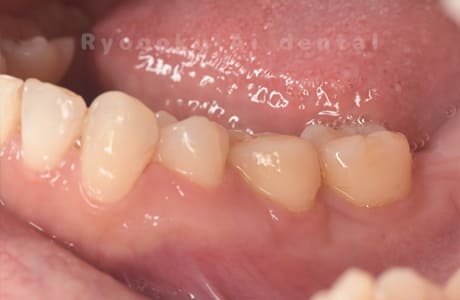

Case27

-

重度カリエス

歯牙移植咬合面術前 -

移植する親知らず

歯牙移植術直後咬合面

歯牙移植術後咬合面

歯牙移植術前側面

歯牙移植術中側面

歯牙移植術後側面

部分矯正術前咬合面

部分矯正術中咬合面

部分矯正術後咬合面

部分矯正術前側面

部分矯正術中側面

部分矯正術後側面

- 原因

- 重度カリエス

- 治療内容

- 自家歯牙移植、部分矯正

- 治療費用

- 220,000円(移植費用)

110,000円(部分矯正費用)

虫歯が大きく、保存不可能となった歯を上の親知らずと交換する自家歯牙移植を行いました。移植歯が小ぶりであったため、部分矯正を行い問題なく噛み合い、経過良好です。

<リスク・副作用>

治療後、痛みや違和感、出血、腫れなどが出る事があります。喫煙者、糖尿病などの方の場合、歯が生着しない場合があります。